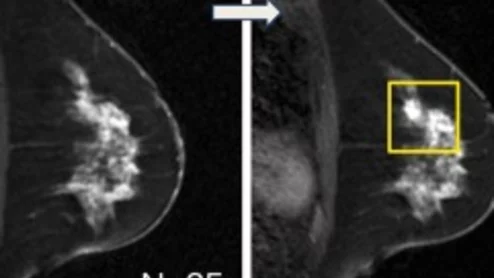

AI model spots missed breast cancers on MRI

Re-evaluation by the second look algorithm could result in a cancer diagnosis up to one year earlier, especially for high risk disease.